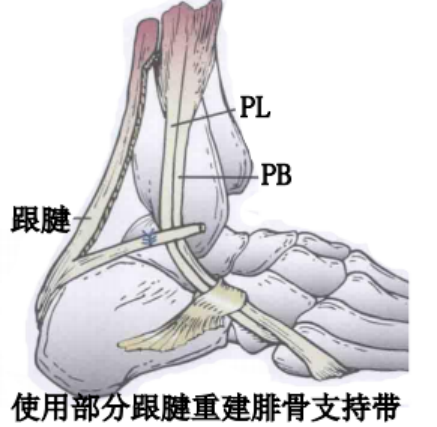

使用跟腱、跖肌腱、腓骨短肌腱等肌腱的一部分加强固定腓骨支持带。